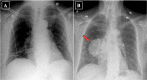

It is well-documented that lung and bronchus cancers are the leading cause of cancer death in the United States in both male and female patients, with lung adenocarcinoma accounting for the highest prevalence of lung cancers. Significant eosinophilia in the setting of lung adenocarcinoma has been documented in a few reports, being described as a rare paraneoplastic syndrome. We report on an 81-year-old female with hypereosinophilia-associated lung adenocarcinoma. A chest film showed a right lung mass, which was not apparent on a chest film 1 year prior, in the setting of significant leukocytosis of 27.90 x 103/mm3 with eosinophilia of 6.40 x 103/mm3. A computed tomography (CT) chest, obtained during admission, demonstrated significant right lower lobe mass enlargement since the previous study completed 5 months prior, with new occlusion of bronchi and pulmonary vessels to the region of the mass. Our observations are consistent with prior reports showing that the presence of eosinophilia in lung cancers may indicate rapid disease progression.